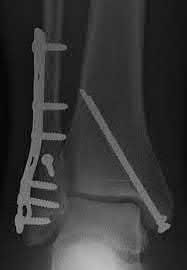

Figure A shows a patient after an open reduction and internal fixation of a bimalleolar ankle fracture.

Egol et al showed that by nine weeks, the total braking time of patients who had undergone fixation of a displaced right ankle fracture returns to the normal, baseline value.

Egol et al, also found that appropriate braking time returns at a point 6 weeks after initiation of weightbearing after treatment of lower extremity long bone and periarticular fractures, as examined with a driving simulator. No differences were seen in return of braking time between periarticular fractures and long bone injuries.